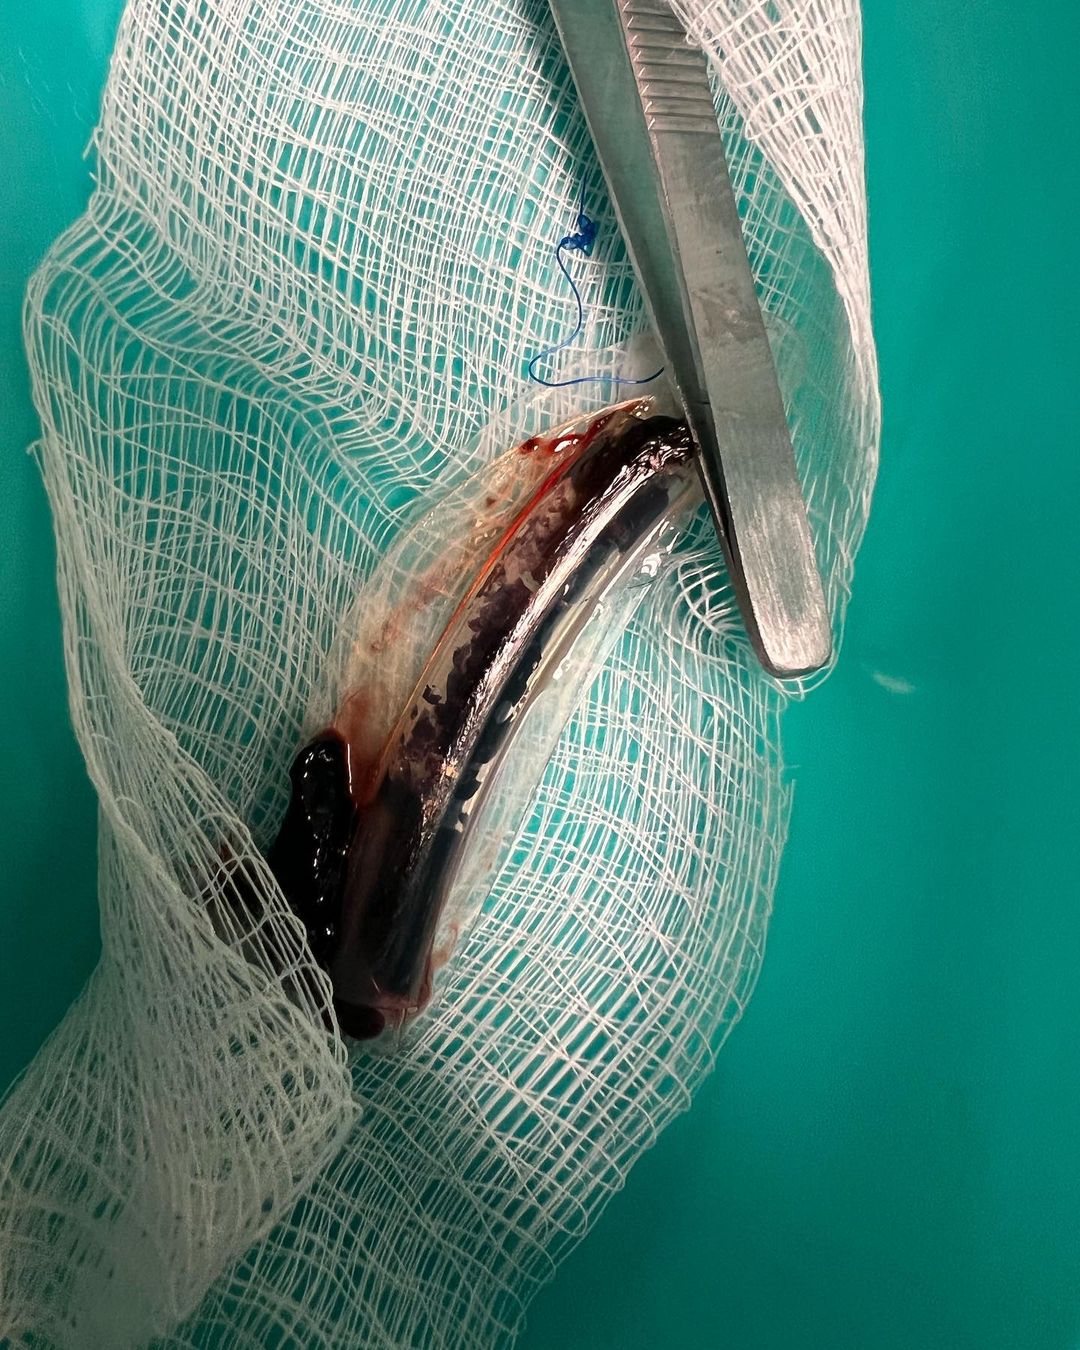

He revealed he had to undergo surgery because the infection had gotten worse over the years and had blocked half of his right face and nostril and was only breathing from his left nostril.

According to him, doctors had told him that the infection had already spread to the back of his head and he could get blind or have brain damage as the procedure was a head surgery really close to the brain.

At this point , my only option was to have a surgery as recommended by my Doctor. Surgery date was set for April 12. Suddenly I booked a movie role in Nigeria and shooting starts April 8, my team and I decided to postpone the surgery till after the shoot. While I was in Nigeria the reunion date was also set, so I killed both birds with 1 stone. As soon as the last episode was shot I took the next flight back to NYC May 7, to prepare for my surgery May 13.

Doctor said the infection had already spread to the back of my head and I was told I could get blind or have brain damage has it was a head surgery really close to the brain and I got was extremely scared. The surgery started at 6.30am and was due to be done 12pm, but I couldn’t wake up for another 3 1/2 hours, mehnnn, everyone was scared.